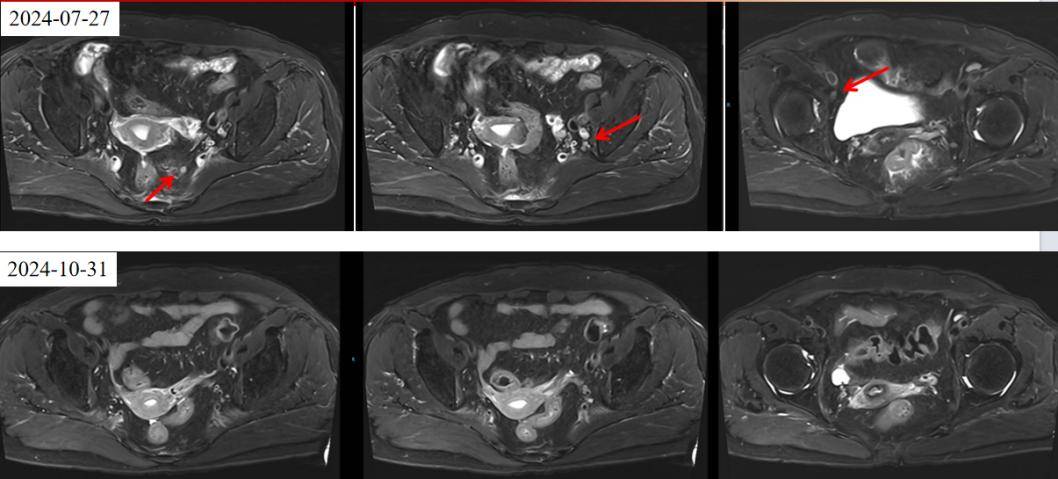

2024年7月27日直肠增强MRI提示:直肠中下段管壁增厚强化(考虑MT)伴周围淋巴结增大,拟T3bN2Mx期,MRF(+)。

疗效评估:2024年10月30日复查CT及MRI,影像评估提示病灶较前明显缩小(肿瘤缩小43%,盆腔淋巴结退缩),疗效评估为部分缓解(PR)。

腹膜后淋巴结消失,既往考虑转移(?)。MDT再次讨论,诊断修正为:直肠腺癌 cT3N2aM1 IVA期。